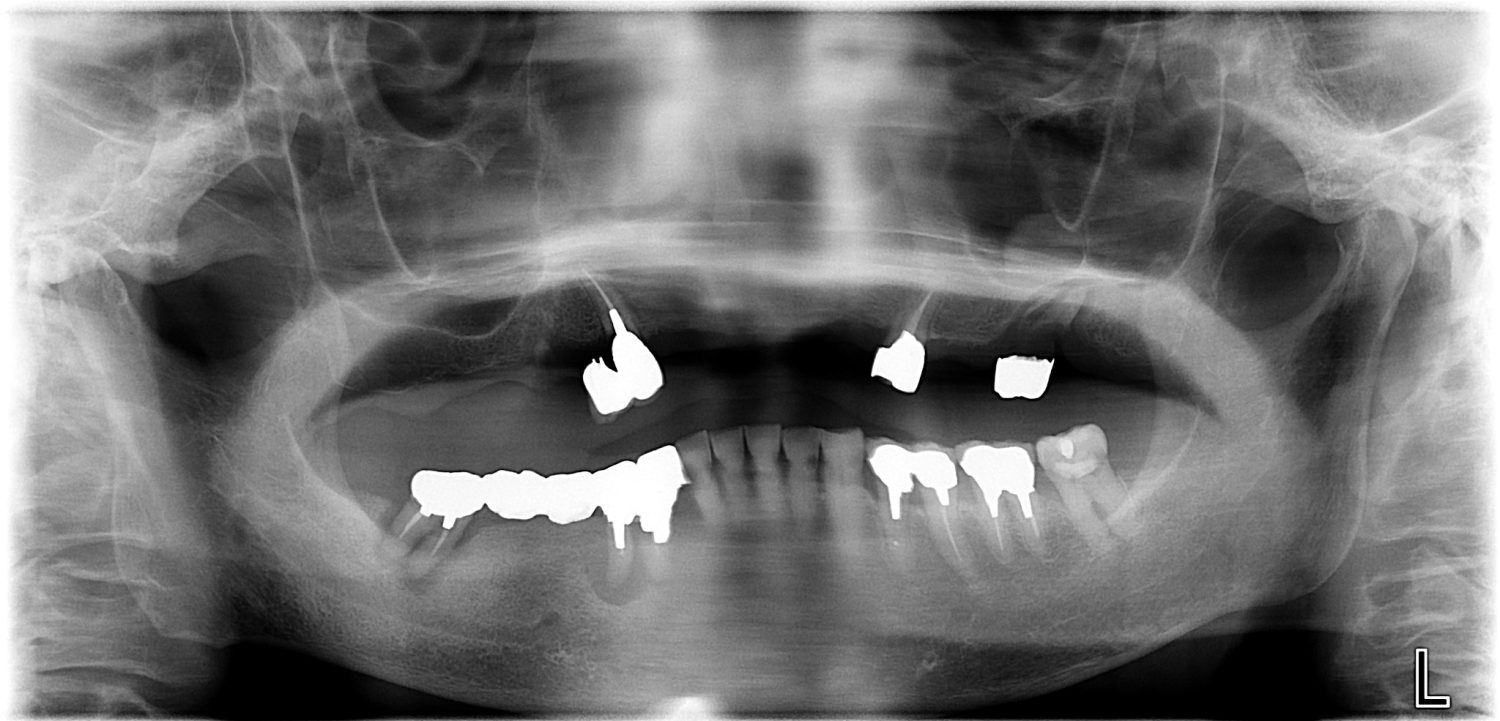

インプラント治療の症例紹介③

Before

After

主訴

むし歯の治療

治療内容

保存不可能な歯の抜歯

下顎にインプラント埋入し咬合再構成

治療費

2,688,400円(税込)

治療期間

14か月

治療回数

21回

想定されたリスク

※上部構造の形態が複雑になるため清掃が難しくなる。インプラント周囲炎の恐れがありました。

濱 仁隆先生

浜歯科

多数歯う蝕および多数歯欠損による咬合崩壊、保存不可能な歯の抜歯により上下無歯顎に。下顎に6本インプラント埋入する事で咬合再構成を行った。